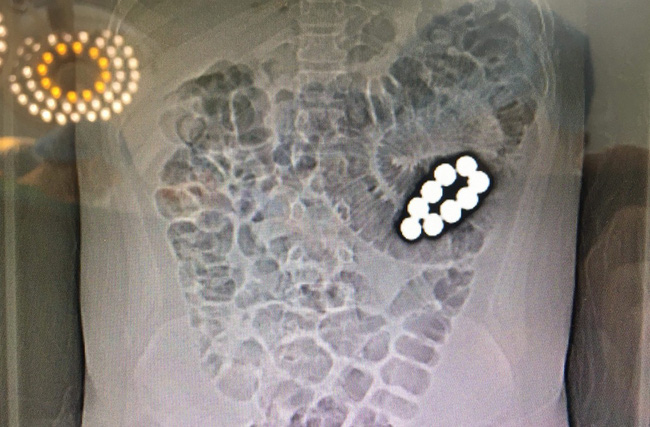

Tại BV, nhà trường được BS thông tin L. có nuốt 9 viên bi sắt nam châm cách thời điểm nhập viện khoảng 2 tuần.

Bi nằm trong ổ bụng được lấy ra vào đêm nhập viện, đồng thời 40 cm đoạn ruột non của bệnh nhi cũng bị cắt bỏ vì hoại tử. Hiện L. đã qua cơn nguy kịch nhưng vẫn còn đau và chưa đi lại được.